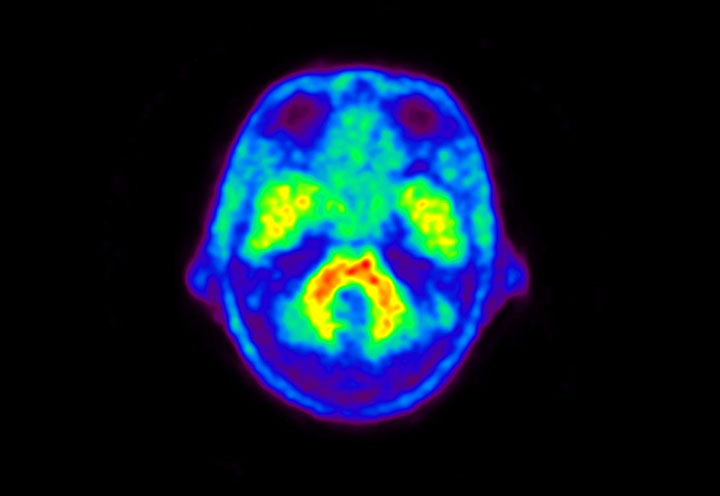

Head / Case5 : Amyloid

Coronal

Courtesy : Kindai University Hospital

- Imaging protocol

- Injected dose: 4.27 MBq/kg, 18F-Flutemetamol

- Uptake time: 99 minutes

- Scan time: 20 minutes